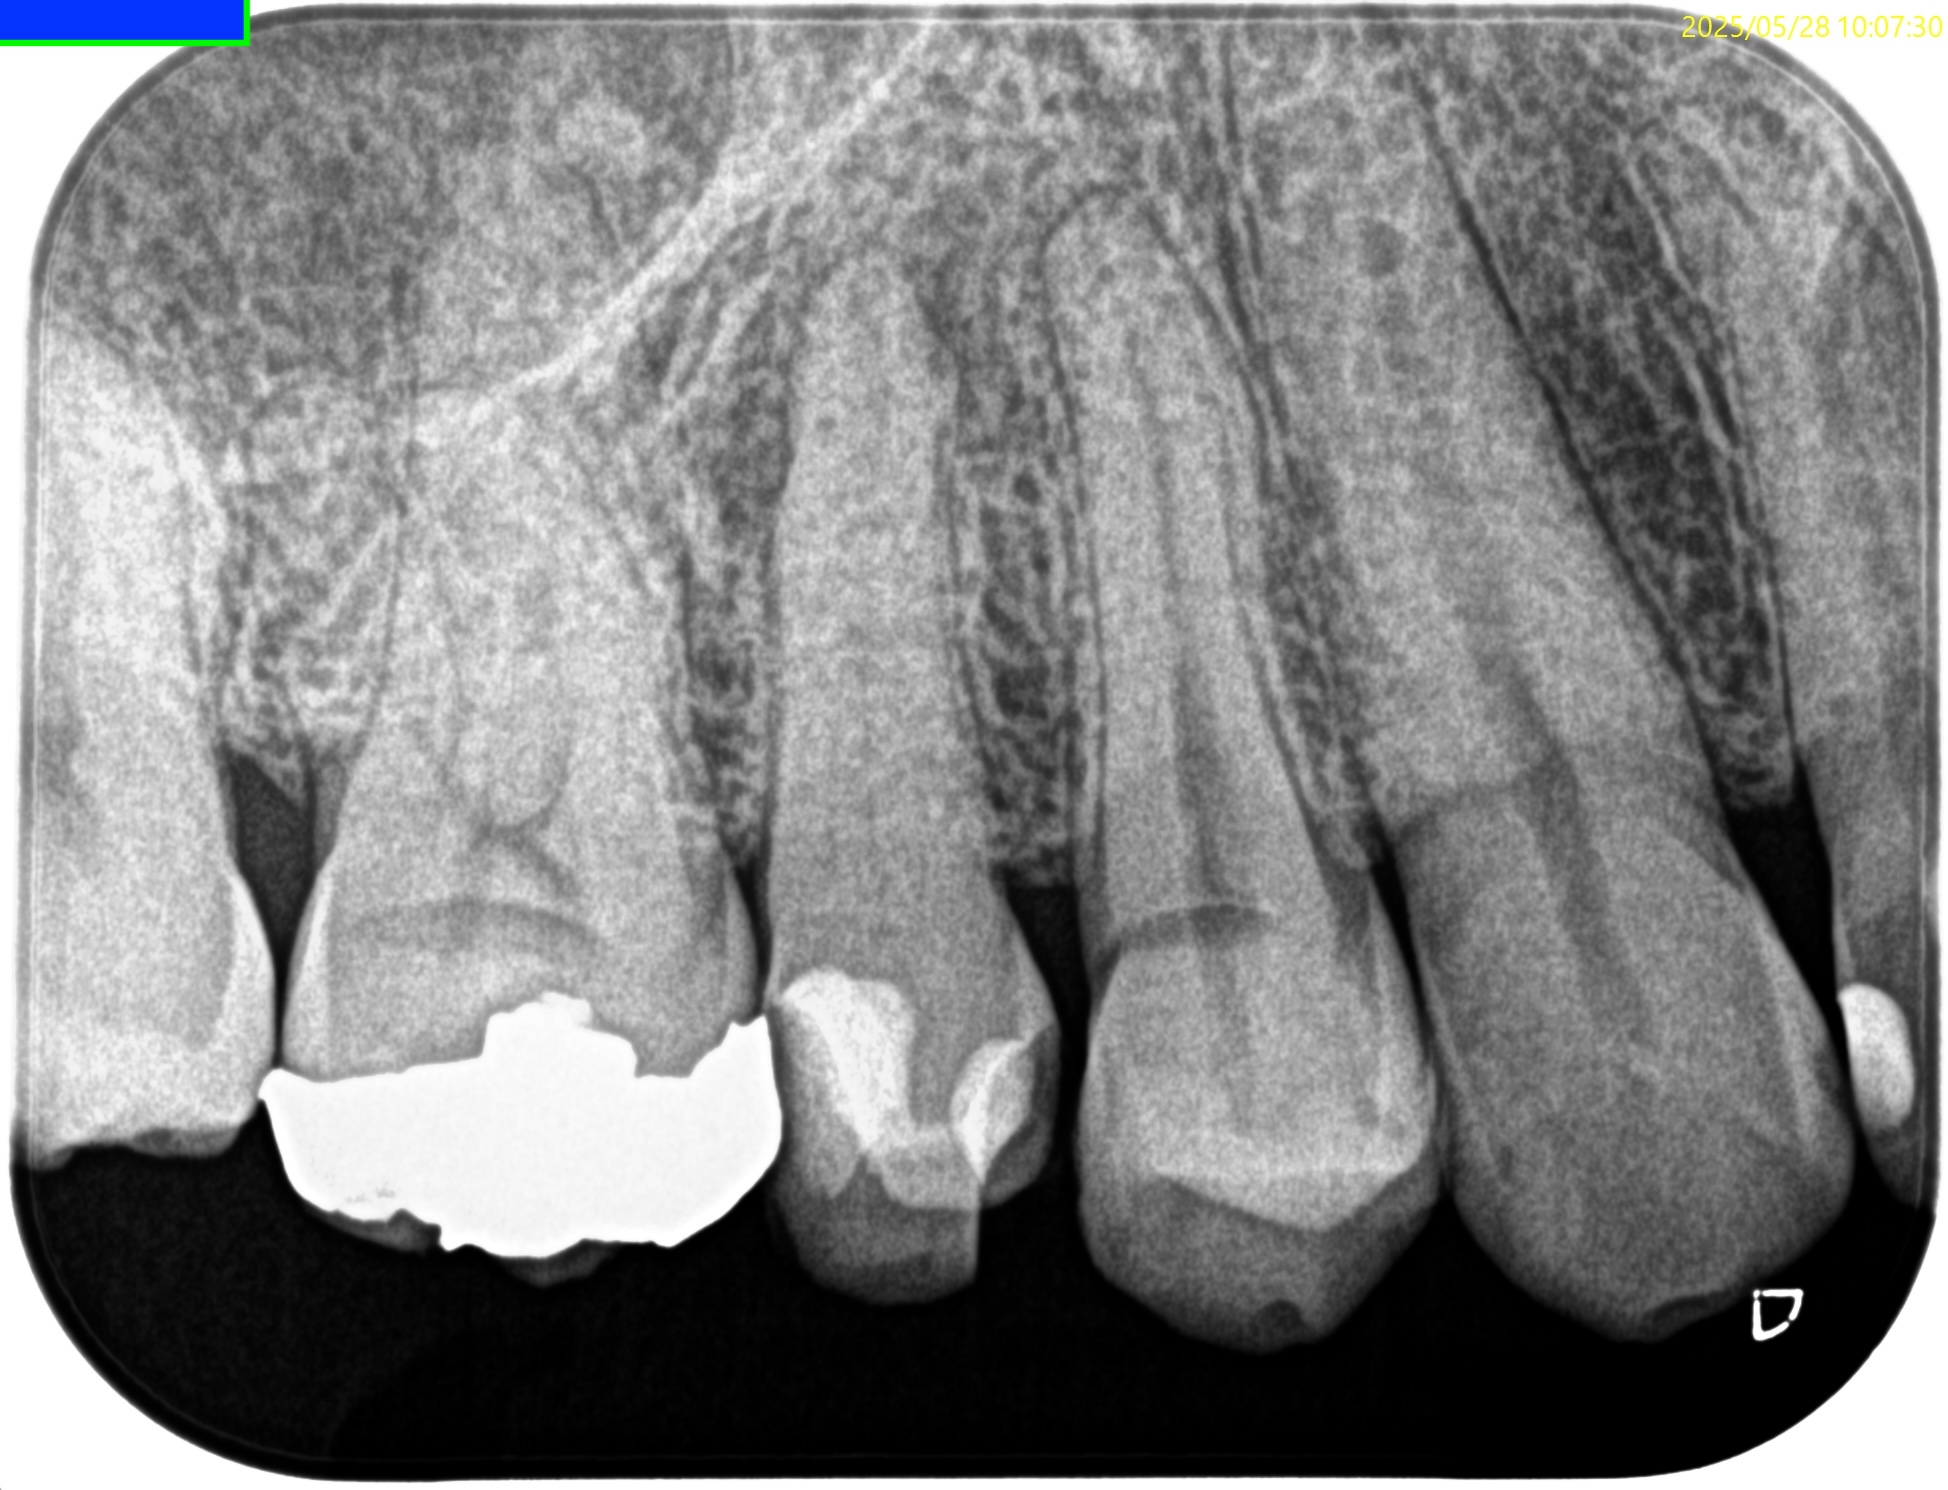

Pre-op Endo test(2025.5.28)

#4 Cold NR/20, Perc.(+), Palp.(-), BT(+), Perio Probe(WNL), Mobility(WNL)

直接覆髄をしたかのような治療が奏功しない状態である。

Pulp Dx: Pulp necrosis

Periapical Dx: Symptomatic apical periodontitis

Recommended Tx: RCT